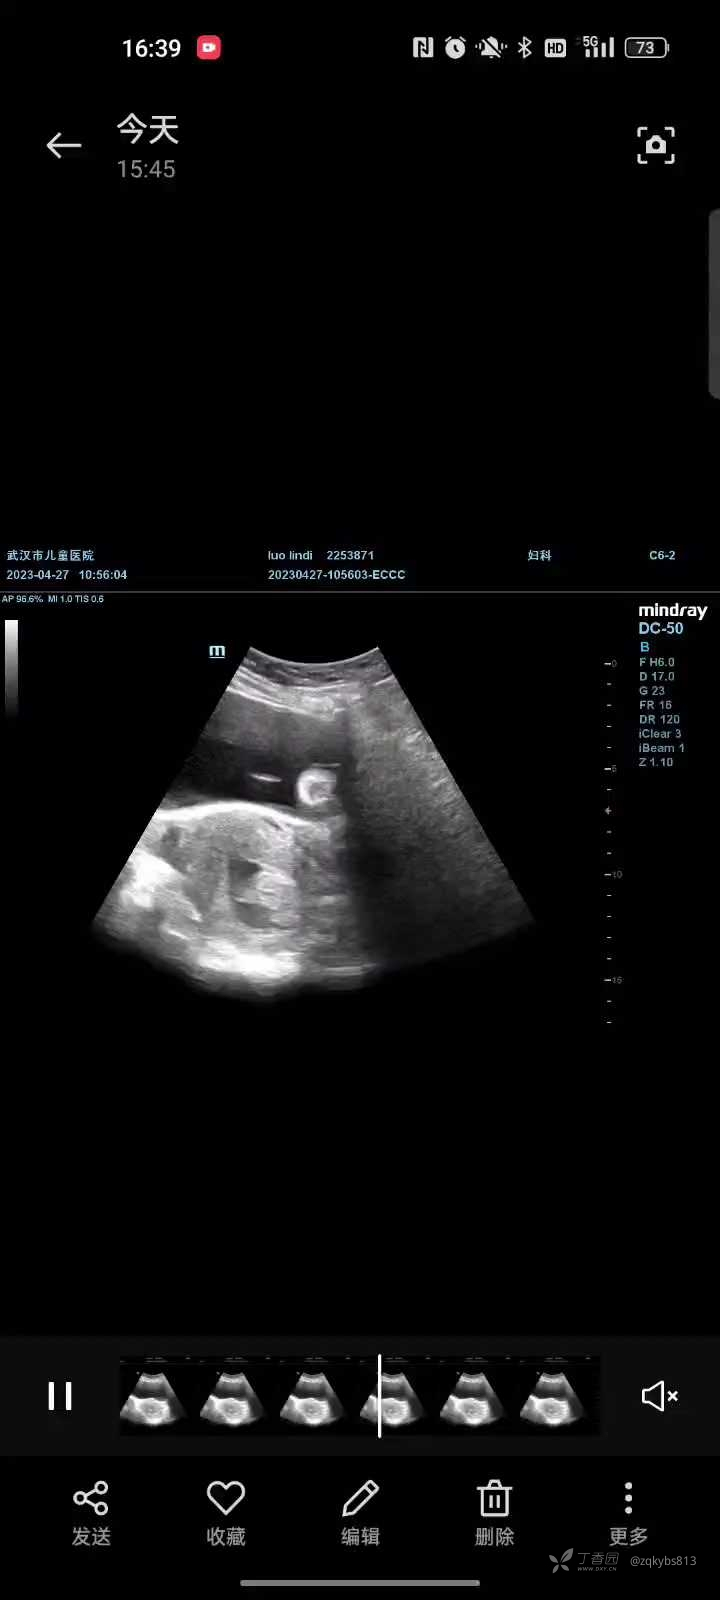

25/4复查HCG12081mIU/ml,彩超如下

26/4行第二次清宫术。考虑第一次清宫时宫腔形态严重变形,还是选择宫腔镜清宫。术中发现宫颈内口至宫腔下段处有一黏膜下肌瘤样凸起肿物,在膨宫液的作用下,术中超声检查发现在肿物与子宫后壁形成的夹角内有约27*20m m等回声,宫腔镜下无法看见,易无法清除